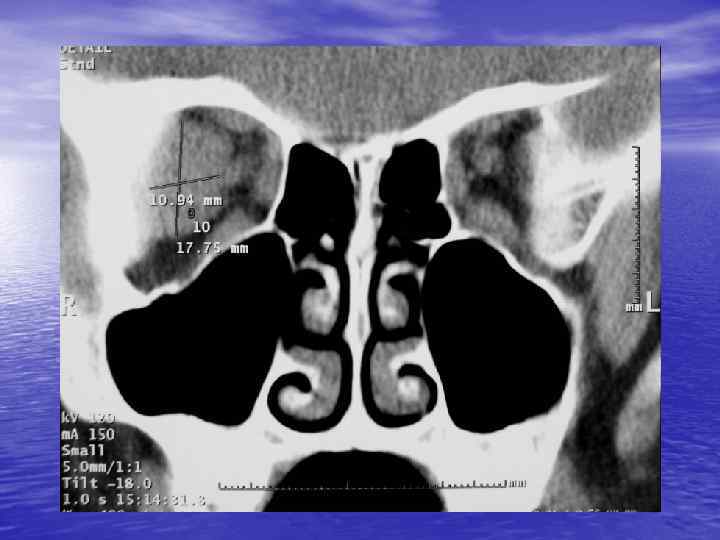

Структурный анализ Оценка основных макроскопических признаков: - положение - форма - размеры - характер контуров и структур патологически измененных участков

Структурный анализ